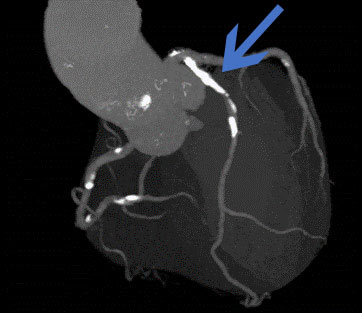

冠動脈CT検査

突然死の原因の1つである心筋梗塞のリスクとなる病変の早期発見に有効です。